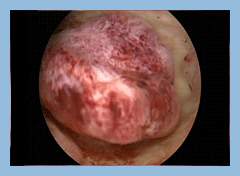

Υστεροσκοπικές εικόνες ενδομητρικού πολύποδαΗ ιατρός Κ.Παπακωνσταντίνου αντιμετωπίζει με εξατομικευμένο τρόπο την κάθε γυναίκα, βασισμένη στα κύρια συμπτώματα της και στην ηλικία της, επιλέγοντας είτε την παρακολούθηση είτε τη χειρουργική αντιμετώπιση των πολυπόδων. Έχει μια σημαντική εμπειρία στην υστεροσκοπική αφαίρεση τους.